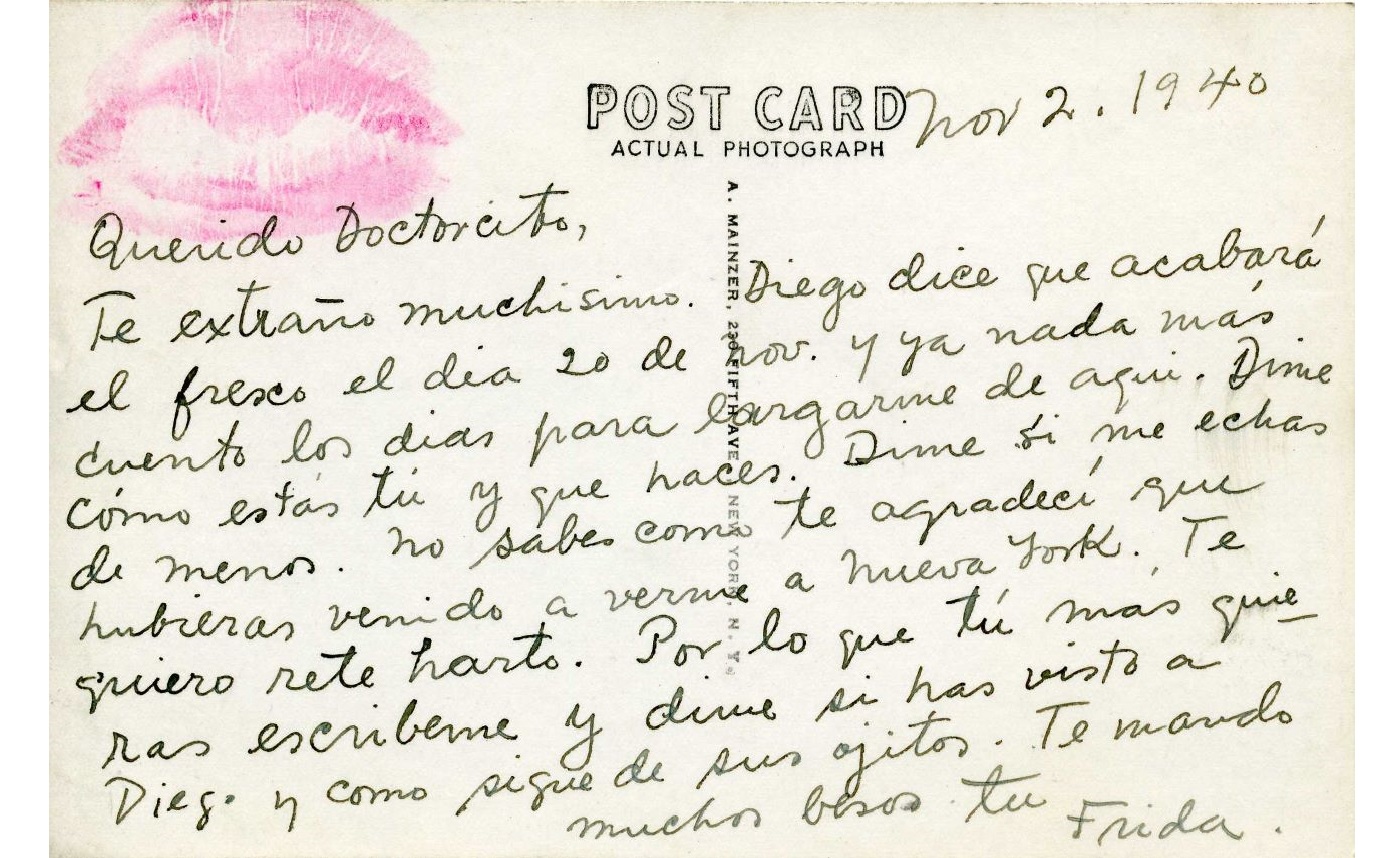

Her Doctors

Suffering from chronic pain and lifelong injuries, Frida Kahlo encountered many doctors, each attempting to provide a medical solution to her health complications. Having undergone over 30 medical procedures, she spent long periods in hospital, eventually developing close relationships with her doctors. She often confided in them, writing personal letters asking for their opinion on her private life—including her marriage—and even painted self-portraits dedicated to them. These doctors were both trusted medical advisors and emotional supports to Frida.Featured artworks

Postcard sent by Frida from New York to Dr. Leo Eloesser, 2 November 1940. © Museo de Filatelia de Oaxaca.

Postcard sent by Frida from New York to Dr. Leo Eloesser, 2 November 1940. © Museo de Filatelia de Oaxaca.